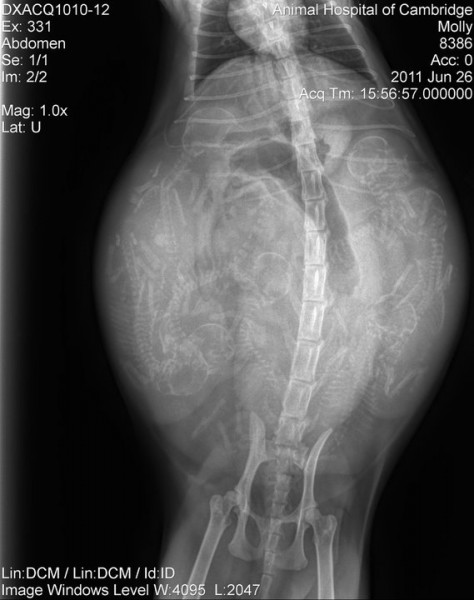

Котят посчитаем? ;)

Вот такая прикольная фотка. Сколько котят у кошки - ваши версии?

черепов насчитала 7. Но вроде больше, там "лишние" позвоночники=))

ееех... сюда плюсанусь))) по черепам 7, по позвонкам вроде 8, а если еще фантазию подключть, то 9 %))))

А да - забыла )) Многие посчитали правильно - котят было действительно 7. А позвоночники с черепами я тоже не сразу состыковала. Справа три котенка это четко видно, а слева 4 - там как раз путанница.

Мы тоже с Ниагарой считали и тоже насчитали 9)))уж больно много позвонков там)))

Хвостики длинные )))

я насчитала 7 по позвоночникам